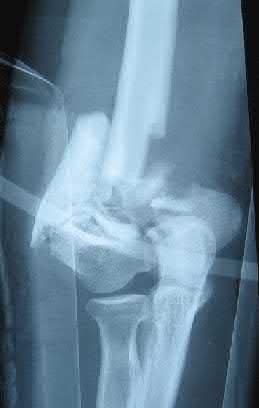

A 28-year-old male sustains a severe hyper-dorsiflexion injury to his ankle in a motor vehicle accident, resulting in a Hawkins Type III talar neck fracture. Which of the following arteries provides the predominant blood supply to the body of the talus, placing it at significant risk for avascular necrosis in this injury?

Explanation

The artery of the tarsal canal, which is a branch of the posterior tibial artery, provides the dominant blood supply to the talar body. In a Hawkins Type III fracture (talar neck fracture with subtalar and tibiotalar dislocation), the blood supply from the artery of the tarsal canal, the artery of the sinus tarsi, and capsular vessels are disrupted, leading to an avascular necrosis (AVN) rate approaching 100%.